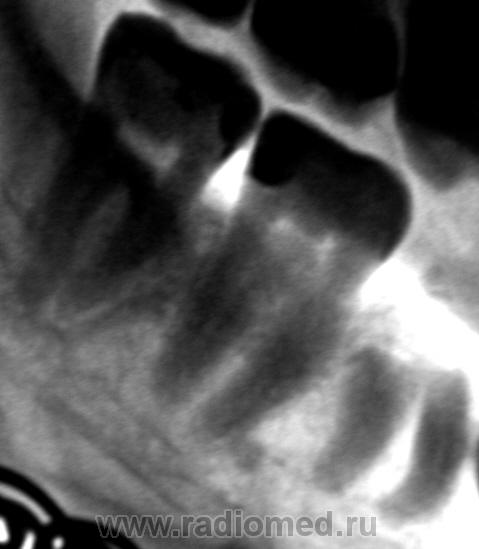

Валентин Львович! Конечно же в первую очередь хочется спросить, а что лечили коллеги? Коронка 6 зуба полностью отсутствует. В области корней перестройка костной ткани литического типа (периодонтин?). В области корней 5 зуба определяется коронка зуба. То ли это зачаток постоянного 5 зуба и коллега до настоящего времени пользовался молочным 5 зубом. То ли это коронка 6 зуба смещенная туда при экстракции. Так что же лечили?

1. Коронку "обломили".

2. Боли, по всей видимости" были обусловлены периодонтитом, но о периодонтите узнали только после проведения рентгенографии.

3. Вы совершенно правы. "Урод" - это зачаток постоянного зуба, который на "на свет" так и не появился.